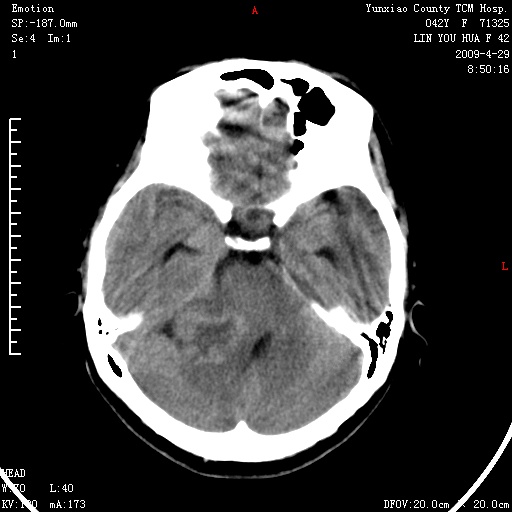

右侧桥小脑角区肿瘤,高密度囊变有显著强化,骨窗见内听道显著扩大,考虑听神经瘤可能性大

1)右侧听神经瘤。2)阻塞性脑积水。